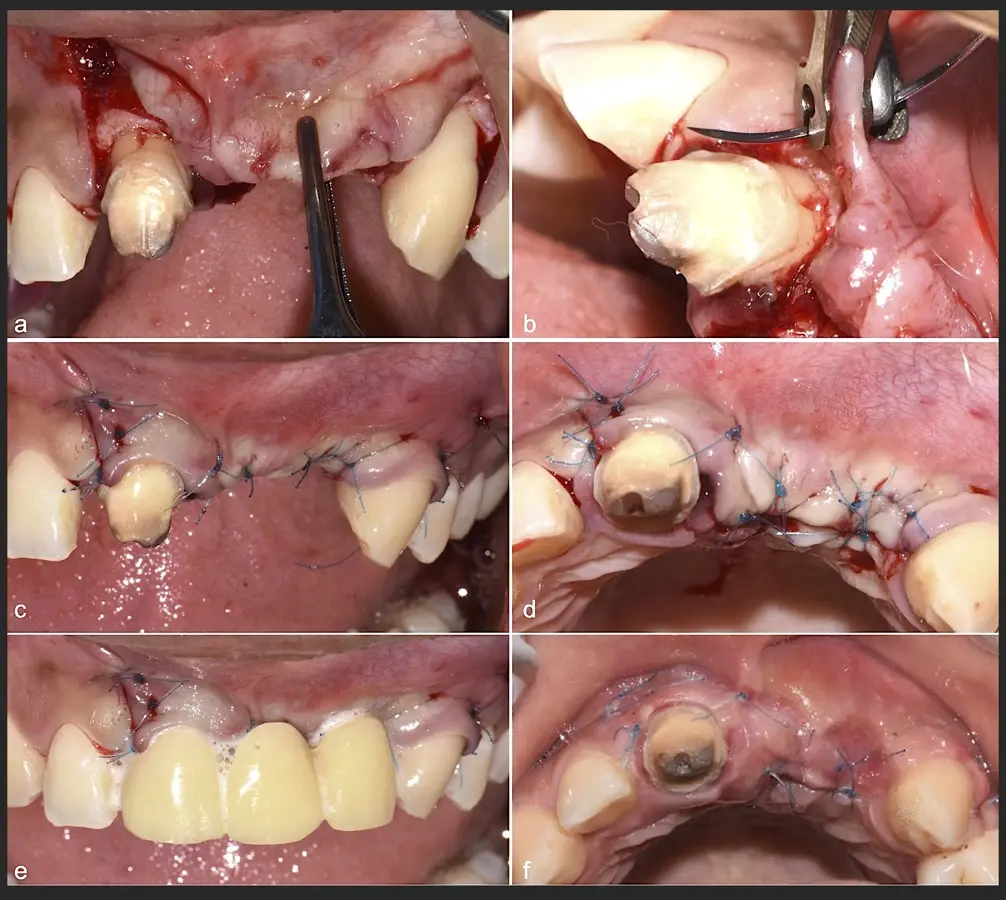

Paciente de sexo femenino de 36 años de edad, llega a la consulta por presentar una restauración protésica inadecuada. En el examen clínico se observa una restauración protésica provisional acrílica sobre las piezas 1.1 y 2.2. Adicionalmente, se aprecia recesión gingival a nivel de la pieza 2.2 y deficiencia horizontal severa de reborde a nivel de la zona edéntula correspondiente a la pieza 2.1. En la evaluación tomográfica se observa ausencia total de tabla ósea vestibular en la pieza 2.2, y se corrobora el déficit en la zona edéntula de la pieza 2.1, para lo cual se indica una reconstrucción de estructuras óseas con hueso en bloque de origen bovino y posteriormente la colocación de implantes dentales.

Figura 34. Vista frontal donde se observa deficiencia vertical del reborde óseo a nivel de las piezas 2.1, 2.2.

Figura 35. Decolado a espesor total sobrepasando la línea mucogingival (a, b).

Figura 36. Defecto óseo y severa reabsorción ósea horizontal: vista clínica (a) y corte tomográfico (b).

Figura 37. Liberación del colgajo para asegurar un cierre sin tensiones.

Figura 38. Decorticalización por medio de broca de 1.2 mm de diámetro (a, b).

Figura 39. Uso del inserto plano de punta aserrado para realizar una mayor decorticalización (a). Surcos de vascularización y nutrición (b).

Figura 40. Secuencia de fijación y modelado del bloque óseo con inserto de corte, eliminación de ángulos agudos (a-d).

Figura 41. Modelado del bloque óseo con inserto plano de punta diamantada (a) para redondear los ángulos agudos y así evitar una dehiscencia o fenestración de los tejidos blandos (b).

Figura 42. El proceso de triturado de biomaterial óseo sustituto en bloque (a - d).

Figura 43. Colocación del biomaterial triturado (a - d).

Figura 44. Pasos para la colocación de la membrana de barrera (a - d).

Figura 45. Afrontamiento de colgajo y sutura (a - e). Control a los 7 días postquirúrgico (f).

Figura 46. Control a los 10 días post cirugía.